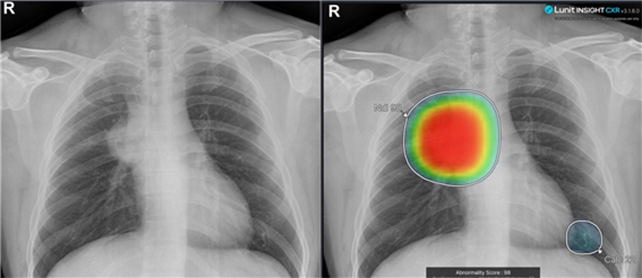

우선 실제 진료한 몇 개의 사례를 설명하고자 한다 아래 사진은 개원 후배의 진료 사례이며 촬영 후 인공지능 판독 소견에서 림프종 의심 소견이 나와 바로 상급 병원으로 의뢰하였으며 조기에 중증 질환을 발견하여 환자에게 감사 인사를 받은 사례이다.